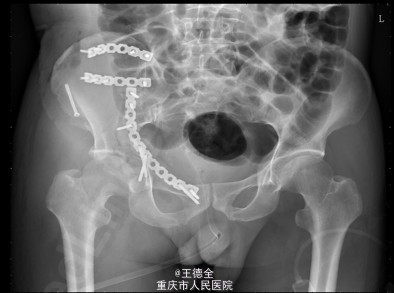

患者男性,51岁,因“高坠伤致左腰部及右髋部疼痛伴活动障碍3天”入院。

查体:急性痛苦面容,神志清楚,平车送入病房,右髋部软组织稍肿胀,局部皮肤完整,未见明显皮疹,挫擦伤及出血点.右股骨髁上骨牵引在位,左腰椎伴明显压痛,骨盆挤压实验阳性,可扪及骨擦音,骨擦感.双下肢感觉,活动,血循良好,足背动脉搏动好;右踝关节主动活动受限,被动活动正常。右侧各足趾背伸、跖屈活动正常,其余各关节活动正常。骨盆X线片示:右侧髂骨、髋臼、双侧耻骨上支、右侧耻骨下支多发骨折,左侧髂骨翼骨折,骨盆出入口右侧份形态失常。辅查影像学资料见下图。

初步诊断:右髋臼粉碎性骨折(Judet X 型) ,诊疗计划:完善双下肢静脉彩超等检查;给予预防深静脉血栓、骨牵引治疗;给予止痛等对症支持治疗;密切观察病情变化,根据病情及时处理。